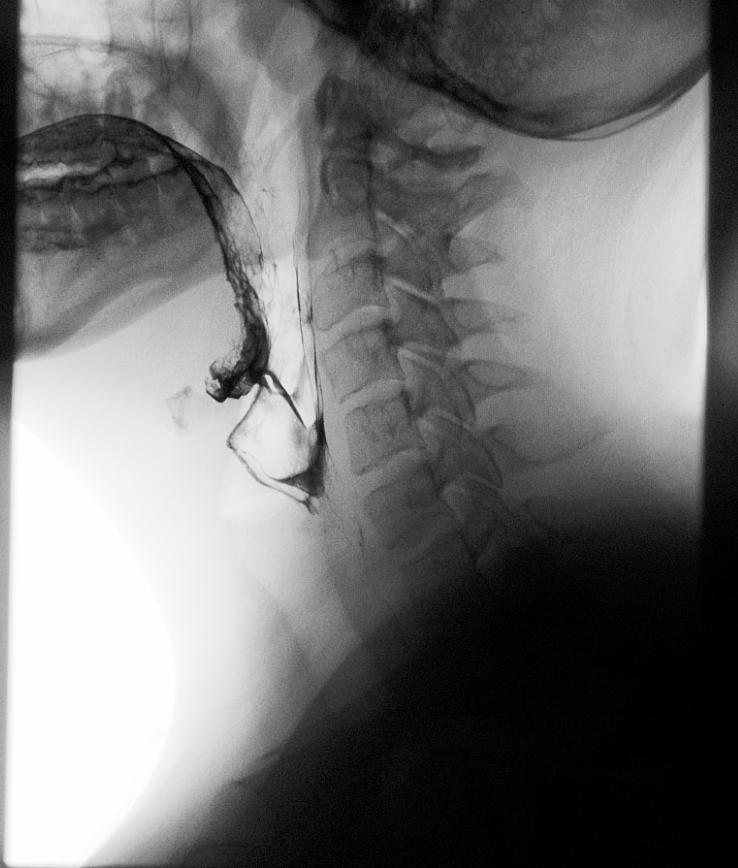

A: My mother worked as interior design coordinator at one of the larger hospitals in the Winston-Salem area. I was visiting her

for lunch one day and we happened to walk through the radiology department “line-up” area which was the hallway between fluoroscopy rooms. I happened to catch a glimpse into one of the rooms where they were performing a modified barium swallow and was immediately captivated. Thus began a lifelong passion and career path!